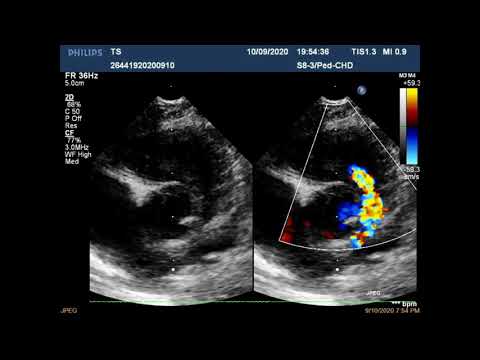

Эхо КГ с анализом тетрада фалло (рус. перевод)